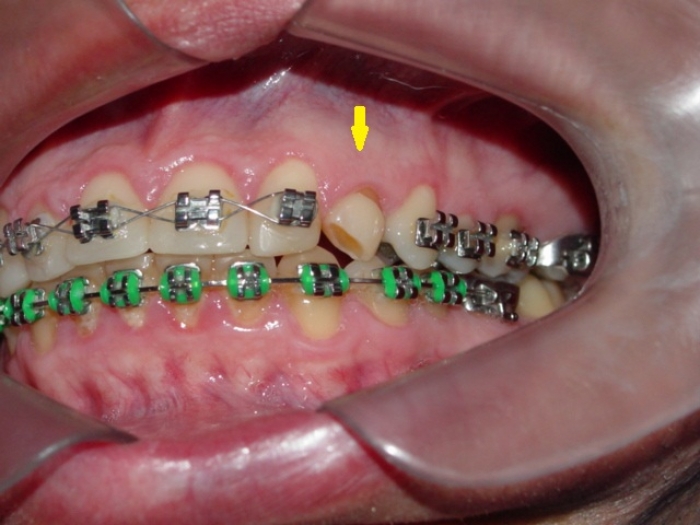

Imagem inicial com presença de canino decíduo